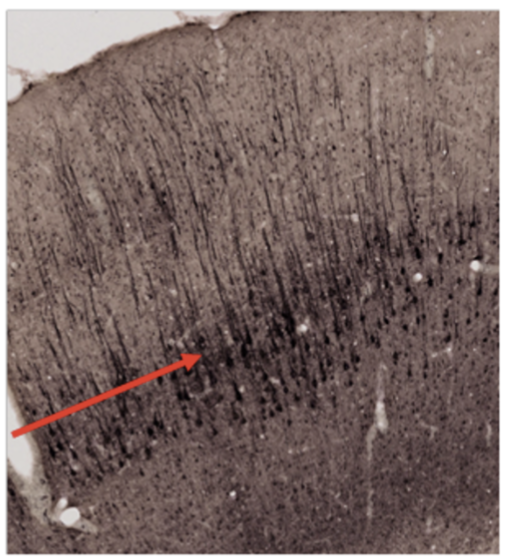

Vilket cellager pekar pilen på? (1p)

Välj ett alternativ:

- A: Lamina molekularis

- B: Lamina multiforme

- C: Lamina pyramidalis externa

- D: Lamina pyramidalis interna

- E: Purkinjecellslagret

- F: Lamina granularis externa

- G: Lamina granularis interna